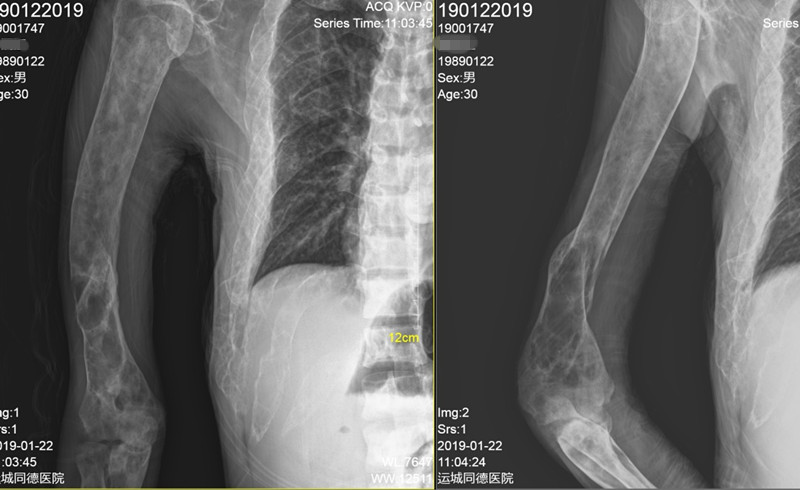

辅助检查:糖化血红蛋白6.2%;甲状旁腺激素87pg/ml(15-65);25-羟维生素D23.63ng/ml(>20) ;血镁0.71mmol/L(0.66-1.07);血钙2.32mmol/L(2.15-2.55) ;血磷0.83mmol/L(0.81-1.45);24小时尿钙3.01nmol/24h(2.5-7.5);24小时尿磷10.9nmol/24h(13-42);TP1NP:1052ng/ml(9.06-72.64);β-CTX :2.68ng/ml(0.043-0.783);骨钙素:255.3ng/ml(24-70);血碱性磷酸酶:691U/L(40-129);血清抗酒石酸酸性磷酸酶:10.3U/L(≤4.47);骨源性碱性磷酸酶:75U/L;人护骨素:110ng/L ;骨密度(DXA):左前臂骨密,Z值-6.9;腰椎骨密度正常;胸腰段正侧位片示:考虑骨纤维异常增殖症伴骨质疏松;颌骨CT示:上颌骨地图样改变,下颌骨囊状空泡、丝瓜瓢状改变,考虑骨纤维异常增殖症;右上肢平片示:囊状膨胀性、丝瓜瓢状改变;胸片:考虑骨纤维异常增殖症。

▼ 右上肢平片: